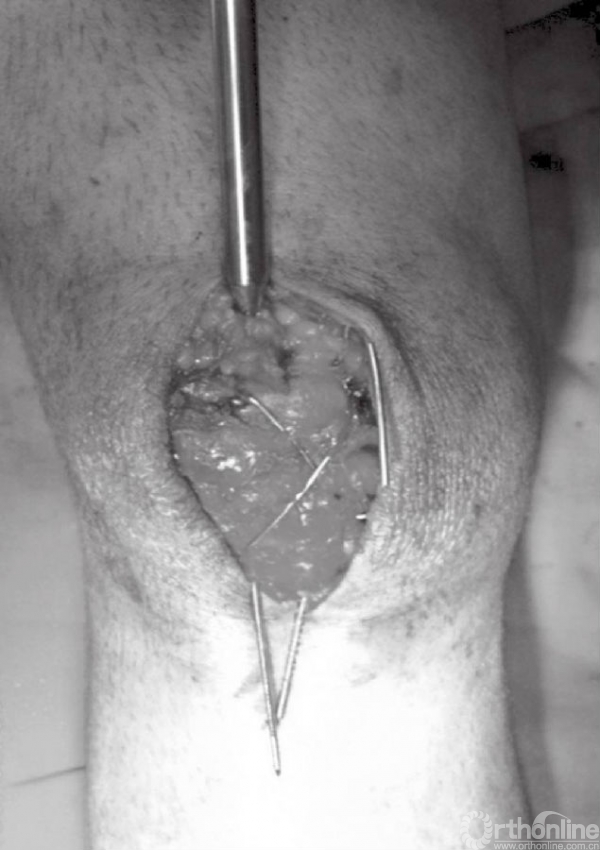

深层显露切口与皮肤切口方向一致。锐性分离深层筋膜,并牵开皮肤组织,进一步切开髌骨囊并清除血肿后骨折端即可显露(图4A和B)。此时,可见髌骨骨折以及撕裂的韧带。以生理盐水清洗血肿以及血凝块(图5)。撕裂的支持带可先辨识后,再进行修复。

图4 A和B切开髌骨关节囊,清除血肿后显露骨折块。图示髌骨横断型骨折,可见韧带撕裂